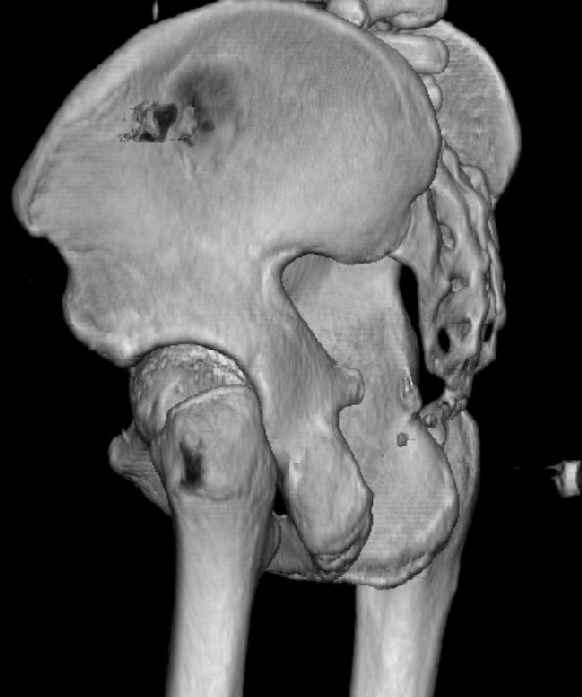

The joint is non-concentric as the head appears to be either "following the caudal segment", or the dome component is displaced from the tethered head... or so it seems... and he's young... so, many fracture surgeons would recommend reduction and fixation.

So we must decide preoperatively which part is the displaced segment?

It's difficult to know from these few selected images which component of the injury (was before and now) should be deemed the "soon to be mobile"

segment. It's my best guess that it is the caudal portion and there exists a healing fracture line somewhere thru the posterior column...one image

suggests it. If true, its early healing/union should be disrupted, and the resultant fragment mobility then allows accurate reduction.

Some more images. Does it help to guess which part of the acetabulum is displaced?

Normal appearing SI joints and a healed posterior column limb... my bet's on caudal segment displacement.